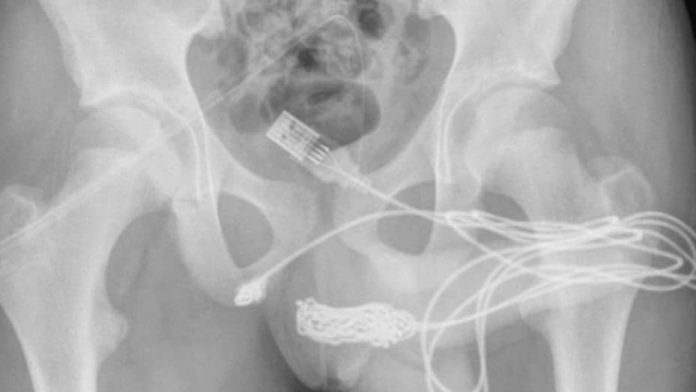

Las radiografías posteriores revelaron que había un verdadero enredo de cable dentro del adolescente. Por ello, los cirujanos hicieron una incisión en la región entre sus genitales y el ano para sacarlo. Primero tiraron del extremo enrollado a través del agujero, cortándolo libre del resto del cable antes de quitar los trozos restantes, literalmente tirando del enchufe.